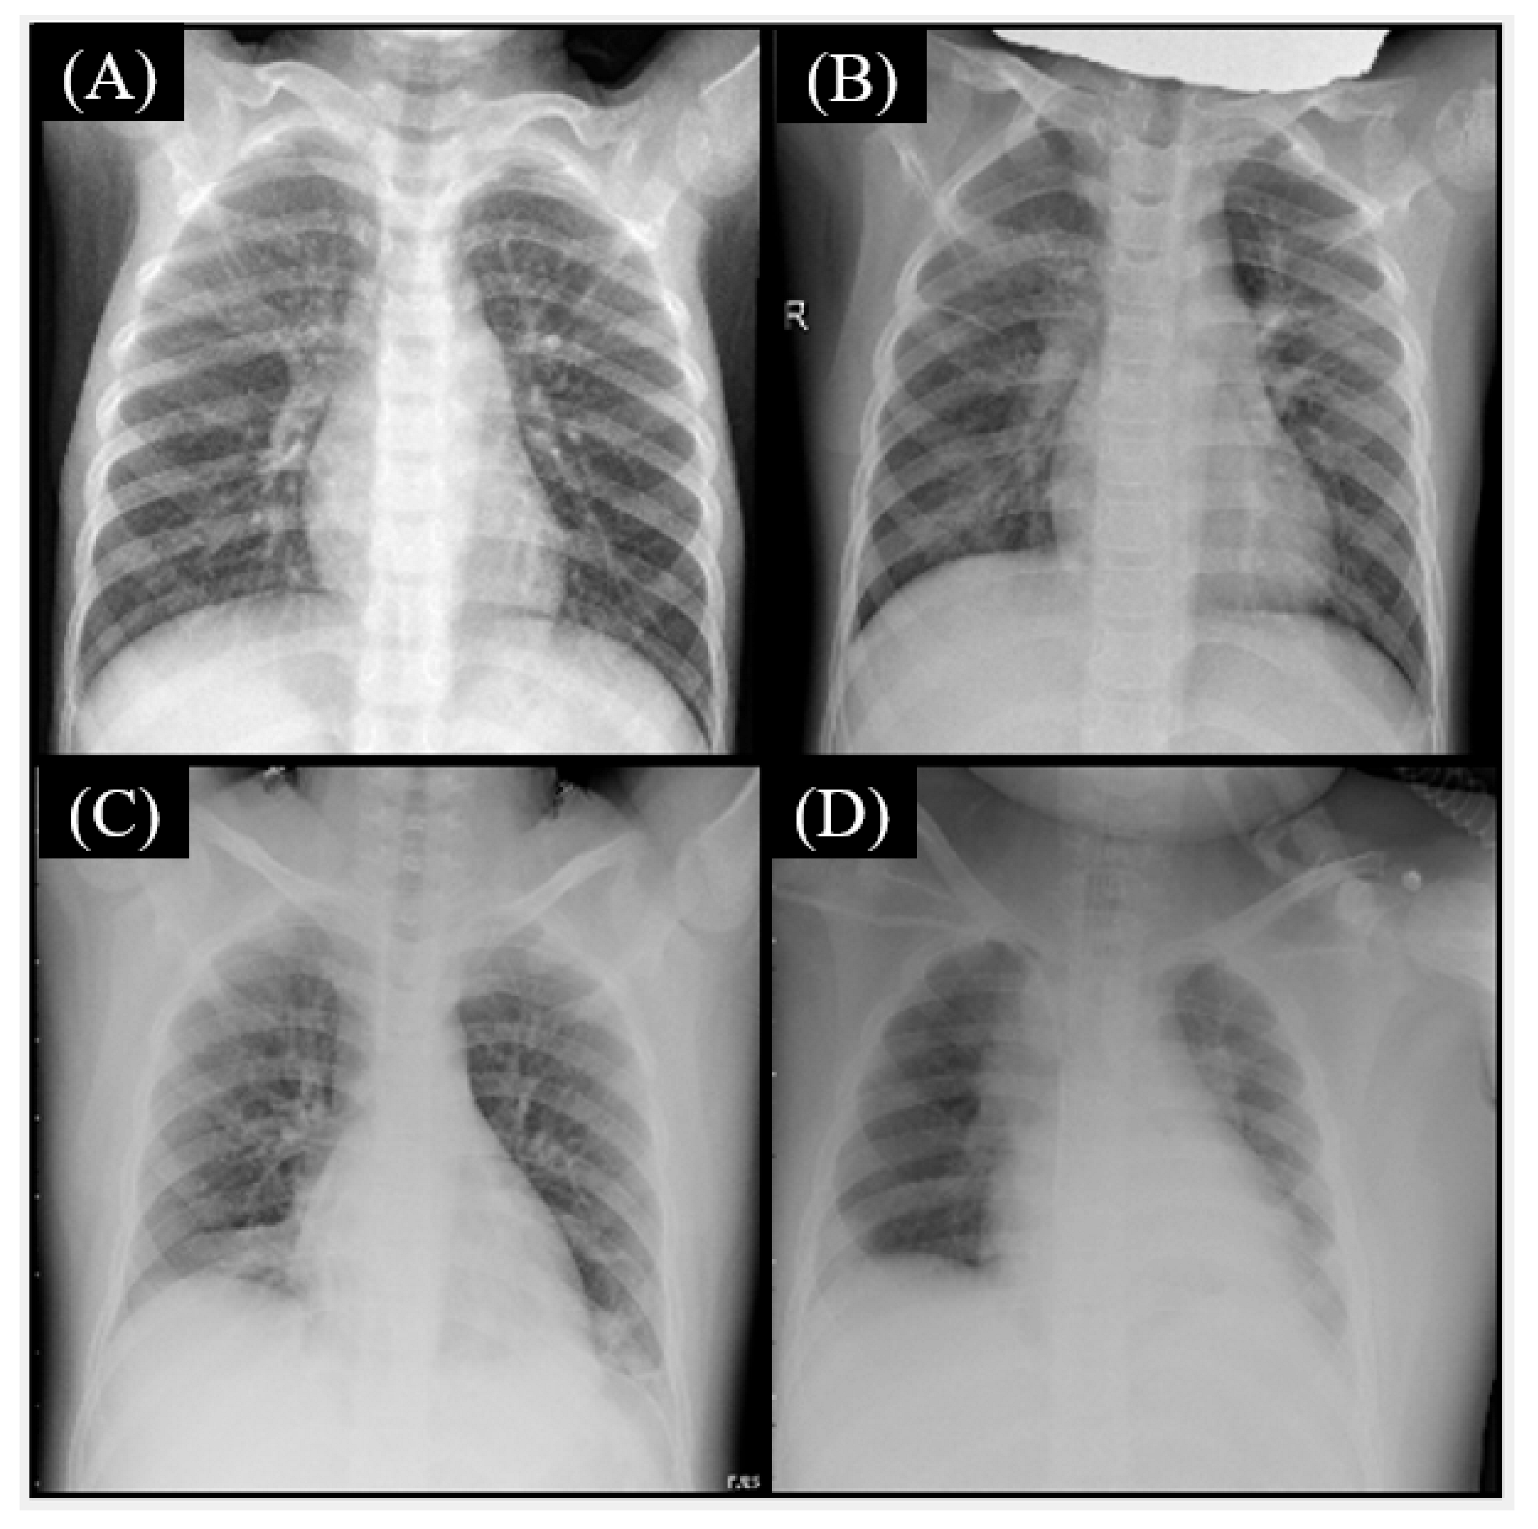

3.2. The Datasets